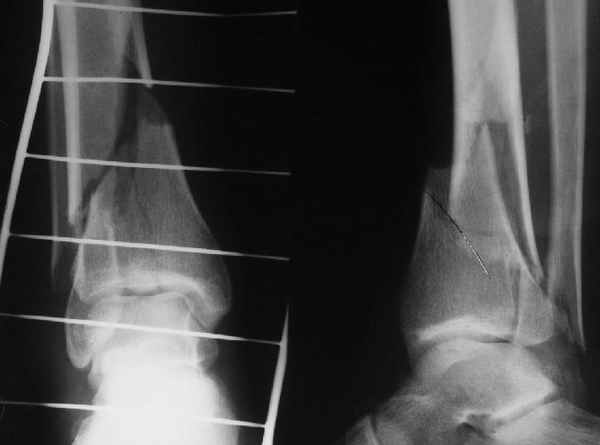

Да и нет! Зависит от перелома и способа остеосинтеза. А результат? (01)

А.Миронов

Кликните для загрузки файла 01.jpg

65KB (66785 bytes)